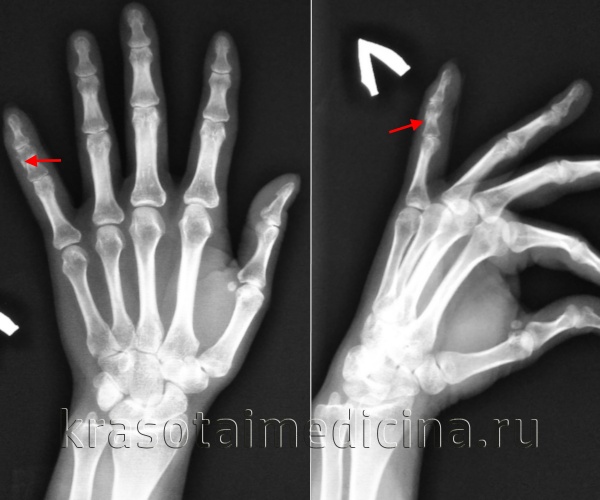

Перелом пальца

Перелом пальца – это нарушение целостности дистальной, средней или основной фаланги пальца руки или ноги в результате травмы. Является широко распространенным повреждением. Может возникать в результате как прямого, так и непрямого травматического воздействия: удара, падения тяжелого предмета, резкого выворачивания и т. д. Проявляется резкой болью, припухлостью, синюшностью и ограничением движений. В ряде случаев наблюдается крепитация и патологическая подвижность. Диагноз уточняют при помощи рентгенографии. Лечение обычно консервативное, в отдельных случаях требуется операция.

Симптомы перелома пальца

В момент повреждения возникает резкая боль взрывного характера. Палец отечен, возможна синюшность или багровый оттенок кожи. Нередко обнаруживаются кровоизлияния под ноготь или под кожу. При смещении фрагментов выявляется деформация и укорочение сегмента. При открытых повреждениях в ране могут быть видны осколки кости. Движения затруднены. Осевая нагрузка болезненна, может определяться крепитация и патологическая подвижность. Функции конечности грубо нарушаются: при повреждении пальца руки пациент не может использовать пострадавший сегмент для захвата предметов и других простых действий, при травме пальца ноги ограничивается опора.

Диагностический поиск осуществляет врач-травматолог. При повреждении верхней конечности диагноз уточняют при помощи рентгенографии пальцев кисти. Снимки выполняют в двух проекциях, с захватом соседних суставов. Для уточнения харатера повреждения при травмах нижней конечности проводят рентгенографию пальцев стопы.